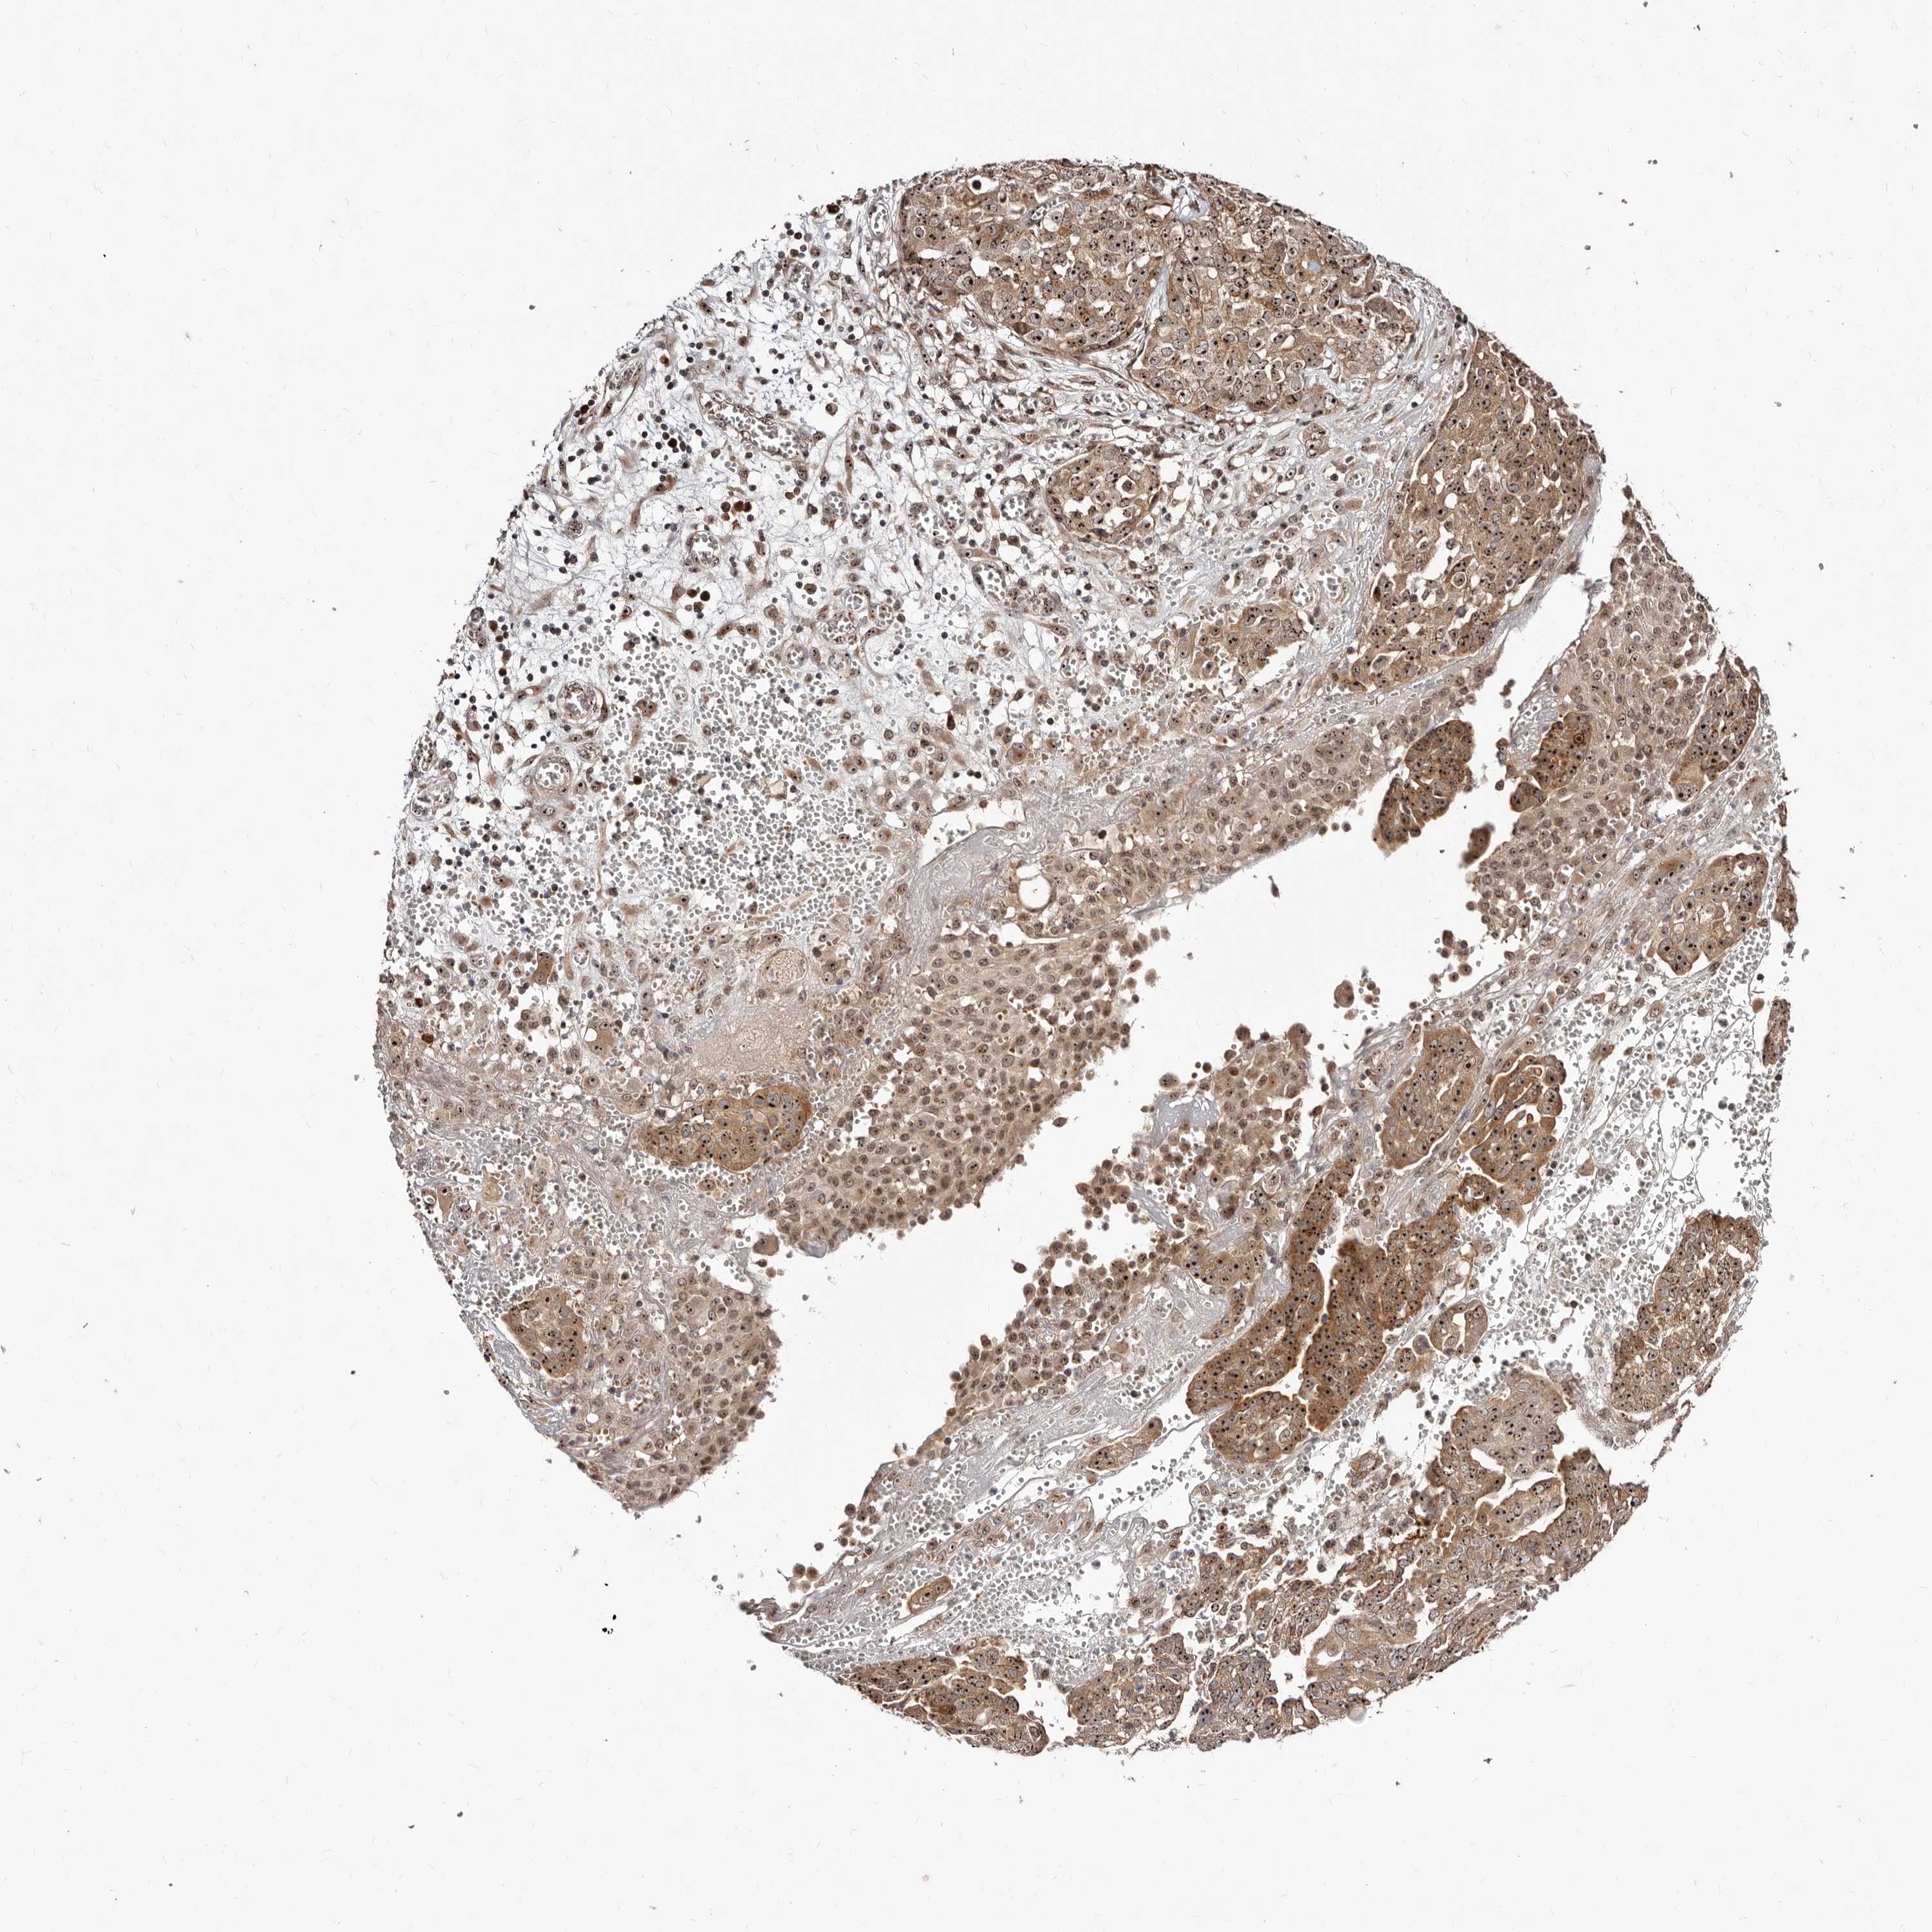

OVARIAN CANCER - Protein expressioni

A mouse-over function shows sample information and annotation data. Click on an image to view it in a full screen mode. Samples can be filtered based on level of antibody staining by selecting one or several of the following categories: high, medium, low and not detected. The assay and annotation is described here.

Note that samples used for immunohistochemistry by the Human Protein Atlas do not correspond to samples in the TCGA dataset.

Antibody stainingi

Antibody staining in the annotated cell types in the current human tissue is reported as not detected, low, medium, or high, based on conventional immunohistochemistry profiling in selected tissues. This score is based on the combination of the staining intensity and fraction of stained cells.

Each image is clickable and will lead to virtual microscopy that enables deeper exploration of all samples and also displays staining intensity scores, fraction scores and subcellular localization as well as patient and tissue information for each sample.

Antibody HPA029165

Antibody HPA029167

Antibody CAB028574

Carcinoma, NOS